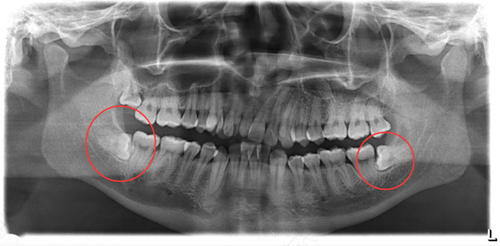

一般去看牙的时候,只要是存在智齿,医生都是会建议患者尽快拔除的。因为智齿如果不拔的话,很容易会引起口腔内发炎,出现肿痛的感觉,会给生活带来一定的困扰。那么,下面的智齿拔有风险吗?

拔除下面的智齿的话,是会有一定风险的。并且如果下面的智齿埋伏的比较深的话,牙科医生在拔起来也会比较困难,还有可能出现术后感染的可能性。因此,无论是在拔智齿前还是拔智齿之后,患者都需要特别注意,避免术中出现大出血,或是术后出现感染等并发症。

在出现智齿后,患者不要因为担心疼痛,而迟迟不去拔除智齿。不然智齿的萌出是可能会挤压到其他牙齿的,并且智齿还会给口腔带来一系列问题。如果平时智齿清洁不干净的话,还容易引起智齿发炎,造成患者牙龈肿痛。